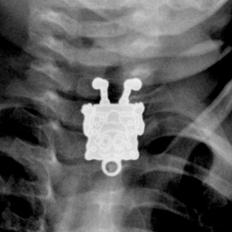

استخرج أطباء لعبة “سبونج بوب” الكارتونية الشهيرة من مرئ رضيع بعد أن استقرت فيه وكادت تودي بحياته لولا التدخل الجراحي.

ونجح الأطباء بمستشفى الملك عبدالعزيز في السعودية في استخراج سبونج بوب من مريء الرضيع البالغ من العمر 16 شهراً.

وأحضر أب طفلهُ الرضيع إلى المستشفى، مخبراً عن أنه ابتلع قطعة غير معروفة، وبإجراء الأشعة فوجئ الأطباء بوجود بوجه سبونج بوب يبتسم لهم في الاشعة السينية ما أصابهم للوهلة الأولي بالدهشة.

وفوراً أجرى الأطباء جراحة للطفل لاستخراج القطعة قبل أن تسبب تهديداً لحياة الرضيع.

و نشرت إحدى أخصائيات الأشعة بمستشفى الملك عبدالعزيز صوراً للأشعة السينية ويظهر فيها سبونج بوب، مشيرة إلى أنها للوهلة الأولى بعد اطلاعها على الصورة الجانبية ظنت أن الطفل ابتلع قلماً، إلا أنها تفاجأت بعد ذلك من الصور الأمامية بأنها قلادة على شكل “سبونج بوب”.